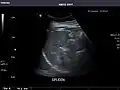

Ultrasound scan of a kidney (right side)

Ultrasonography of the kidneys is essential in the diagnosis and management of kidney-related diseases. The kidneys are easily examined, and most pathological changes in the kidneys are distinguishable with ultrasound.[7]